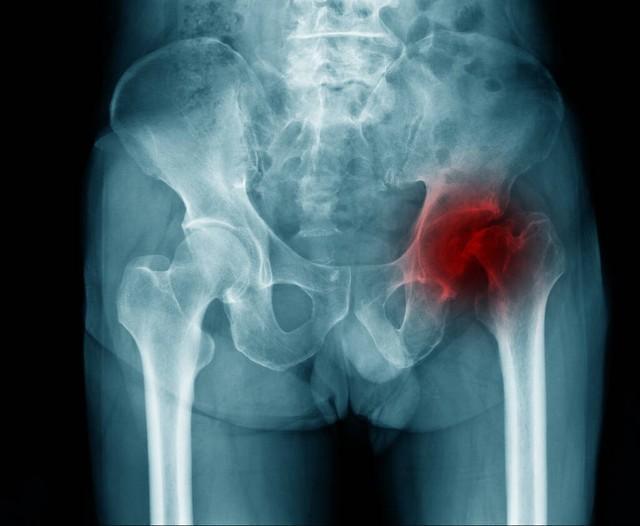

骨頭壞死概述

骨頭壞死是指骨組織因各種原因?qū)е卵汗蛔?,從而使骨細胞死亡和骨組織破壞的過程,骨頭壞死的原因包括創(chuàng)傷、感染、長期應用激素、骨質(zhì)疏松等,骨頭壞死后,患者可能出現(xiàn)疼痛、腫脹、活動受限等癥狀。